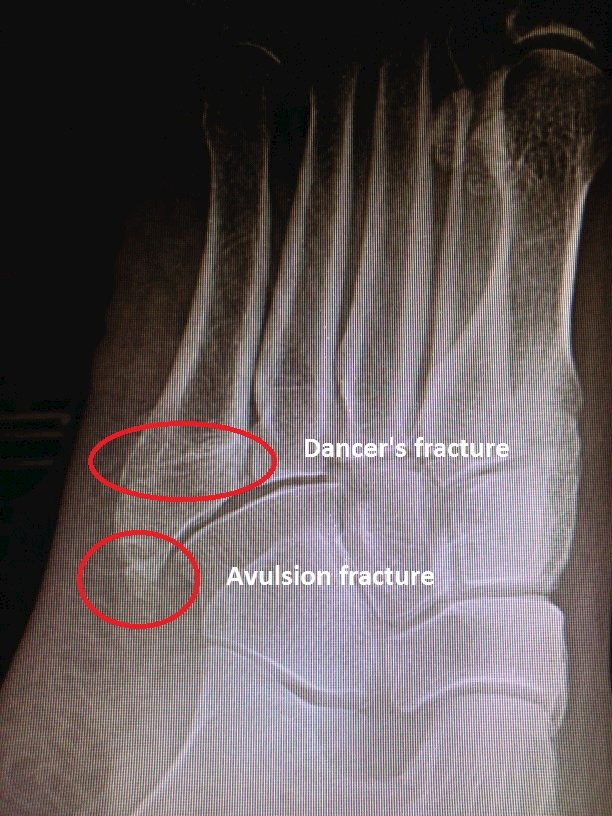

In case #2, the patient is a 64 y/o female who sustained an inversion sprain 8 months ago while at work. The patient is sedentary, a non-smoker and overweight. The initial plain films showed what appeared to be an avulsion fracture at the base of the 5th metatarsal. An avulsion fracture is where a small chip of bone is pulled from the epiphysis (hence the name traction epiphysis). Interestingly though, as time passed, a true dancer’s fracture of the metaphyseal-diaphyseal junction appeared. At 8 months out with continued pain, an MRI was obtained that showed no inflammatory reaction at the site of the dancer’s fracture. The MRI was primarily ordered to rule out tendon pathology to include peroneal tendon tear or tendinitis. The differential diagnosis includes non-union of the 5th metatarsal dancer’s fracture. This patient will likely go on to have internal fixation.